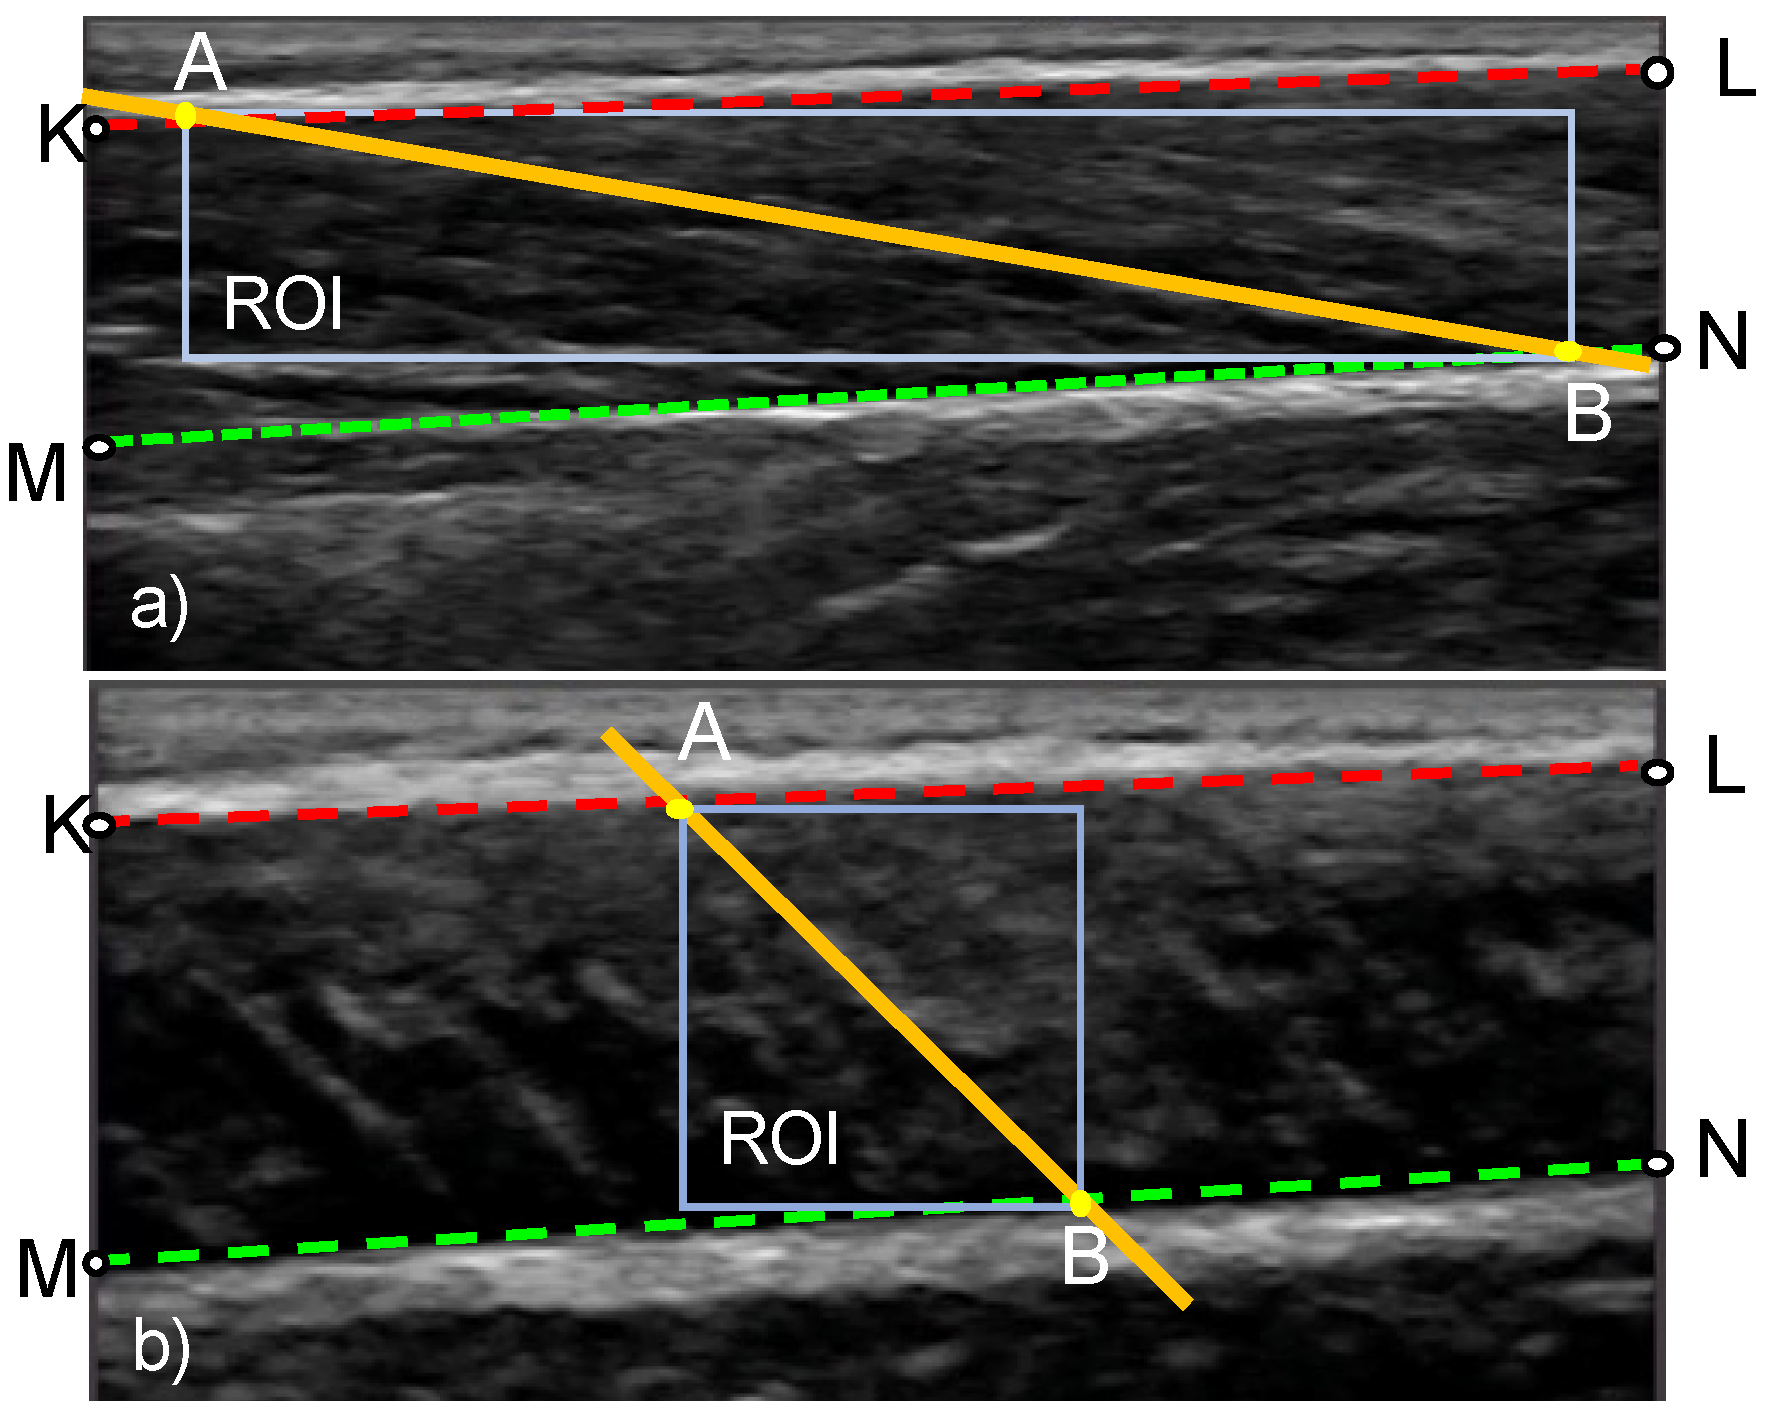

In stage 3, the change in orientation of the fascicles is calculated based on the distortion of a region of interest (ROI) within the fascicle band. The ROI is a rectangle defined by the two insertion points of the fascicle direction line to the aponeurosis lines (points A and B in Figure 5). Once the ROI is defined in the reference frame, the KAZE interest points are identified and tracked in the following frame (tracked frame) using the Kanade–Lucas–Tomasi (KLT) algorithm. To enable the analysis of videos of rapidly changing fascicle direction and length, the ROI is updated and new KAZE interest points defined every two frames throughout the duration of the video (Figure 2). The tracking process is implemented in MATLAB using the pointTracker function. This function uses the optical flow vector (given by the KLT algorithm) to determine the movement of interest points between two frames. Once the new and the old positions of interest points are in hand, the translation (along x-direction and y-direction), rotation, scale (along x-direction and y-direction) and shear/distortion (affine matrix, 6 degrees of freedom) of the ROI is estimated using the estimateGeometricTransfrom2D function in MATLAB. The new position of the fascicle direction line in the tracked frame is found by applying the affine matrix given by the estimateGeometricTransform2D function over the coordinates of the fascicle direction line in the reference frame. Once the analysis of the first two frames is complete, the tracked frame becomes the new reference frame and the entire process is repeated (Figure 2).

Figure 5.

Definition of the region of interest (ROI) in an ultrasound image of a muscle at rest (a) and during maximal contraction (b). The geometric points that are used in the calculation of FL and PA are also shown. Lines KL and MN, respectively, correspond to the top and bottom boundary of the fascicle band. Points A and B denote the insertion points of the fascicle direction line.

The hyperparameters associated with the MATLAB function for finding the KAZE interest points in the reference frame are: (1) rectangular ROI, specified as a row vector of the form [x, y, width, height] where x, y denotes the x-coordinate and y-coordinate of the starting point of the rectangle (top left corner) (Figure 5), width and height denote the width and height of the rectangle respectively (2) number of scale levels and number of octaves for multiscale analysis and (3) method to compute diffusion (conductivity). To enable multiscale analysis, the number of octaves should be an integer that is greater than 1 and more features can be detected when the number of octaves is more. Similarly, the number of scale levels is an integer in the range [3, 10] and smooth-scale changes can be achieved if the number of scale levels is high. For our experiment, the rectangular ROI was defined as [Ax, Ay, width = Bx − Ax, height = By – Ay], where Ax and Bx are the x-coordinates of points A and B respectively (Figure 5); Ay and By are the y-coordinates of the points A and B respectively (Figure 5); the number of octaves and number of scale levels were set to 9 and 5 respectively.

2.4. Stage 4: Calculation of PA and FL

After obtaining the new position of the fascicle direction line and the boundaries of the fascicle band, the insertion points of the fascicle direction line (points A and B in Figure 5) are determined, followed by the computation of FL as their Euclidean distance. PA is calculated as the angle between the fascicle direction line and the deep aponeurosis (angle ABM in Figure 5).